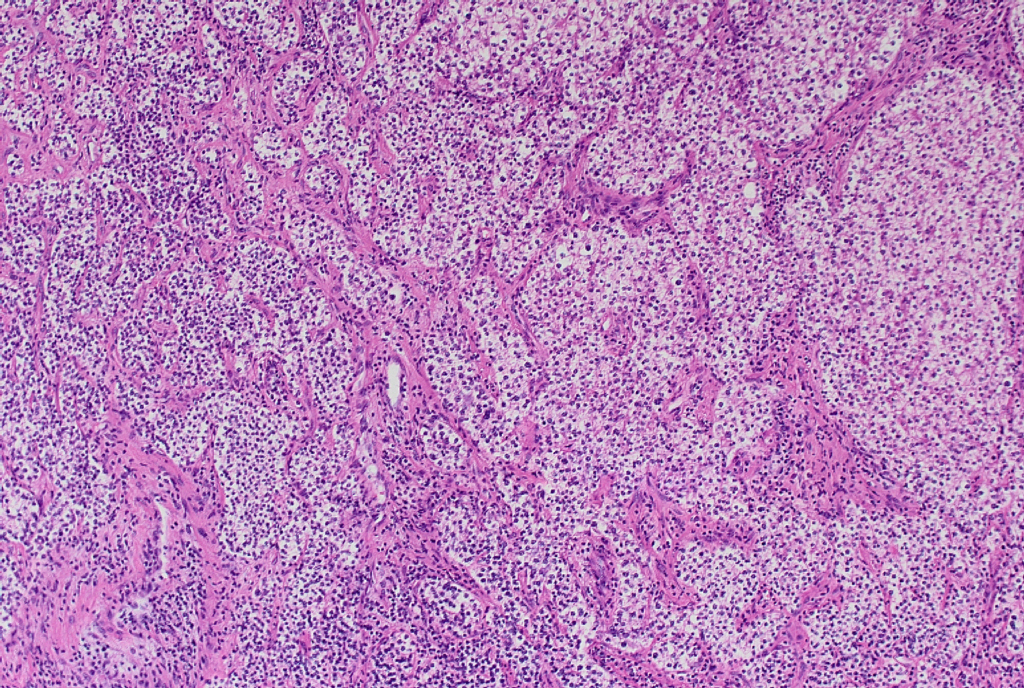

細胞像は裸核状で大小不同がみられるが、核形不整には乏しい細胞が多くみられる。

手術後の組織診の免疫染色にてカルシトニン陰性、クロモグラニンAとシナプトフィジン陽性の結果より、副甲状腺癌と診断された症例であった。

解説後、改めて細胞像を観察し、神経内分泌腫瘍の細胞であることを確認した。

HE カルシトニン クロモグラニン シナプトフィジン